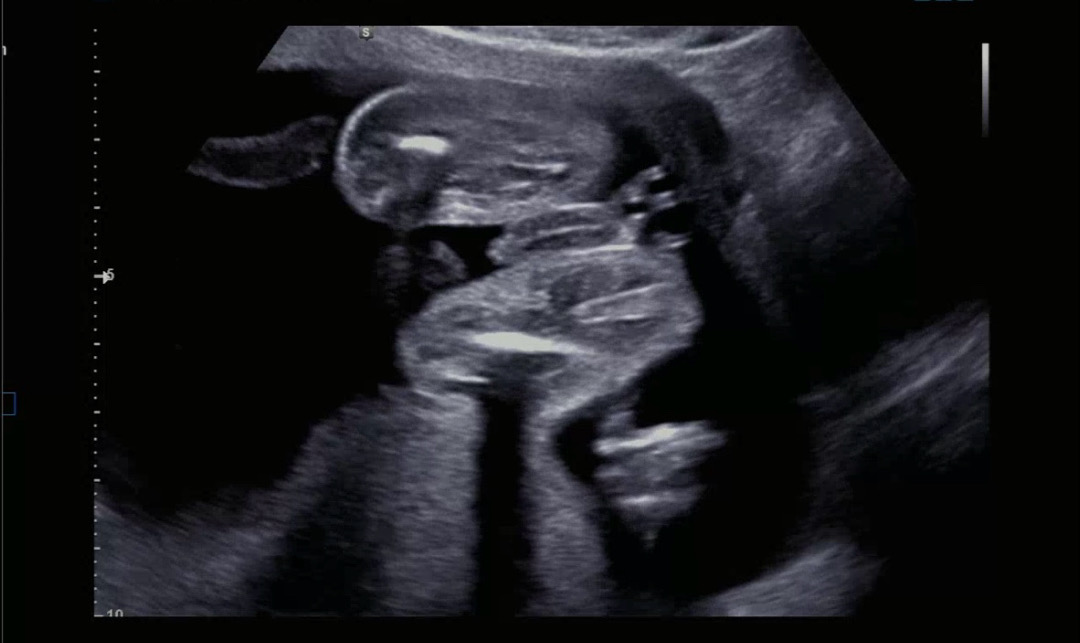

아기 성별이 뭘까요???

의사 선생님이 애매모호하다고 하시는데 여러분은 어찌 보이시나요???

아들같아요..!! 제가 올린 사진이랑 비교해보면 다리사이에 뭔가 보이네용 ㅎㅎ